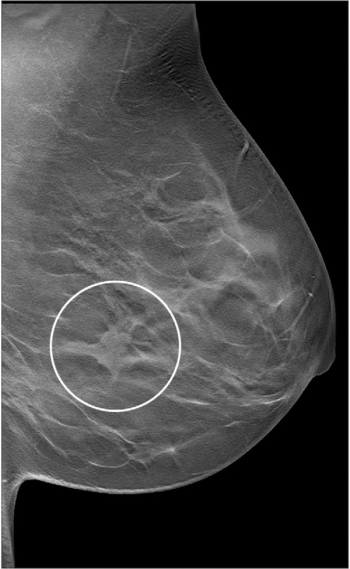

For women with dense breasts, abbreviated breast MRI and digital breast tomosynthesis (DBT) both offered greater than 98 percent sensitivity rates and greater than 94 percent negative predictive values (NPVs) for breast cancer detection, according to newly published research.

In a study of over 30,000 screening digital breast tomosynthesis (DBT) exams for over 8,000 women, researchers found a specificity rate of 95.1 percent, a false negative rate of 2.1 (per 1,000 exams) and an abnormal interpretation rate (AIR) of 5.7 percent.